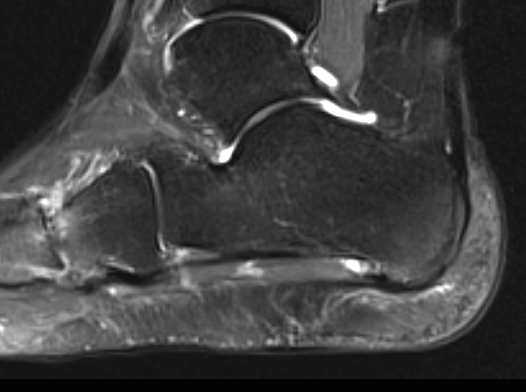

MRI

Thickened plantar fascia with tears

Exclude - retrocalcaneal bursitis / calcaneal stress fracture / Baxter's neuroma / tarsal tunnel syndrome